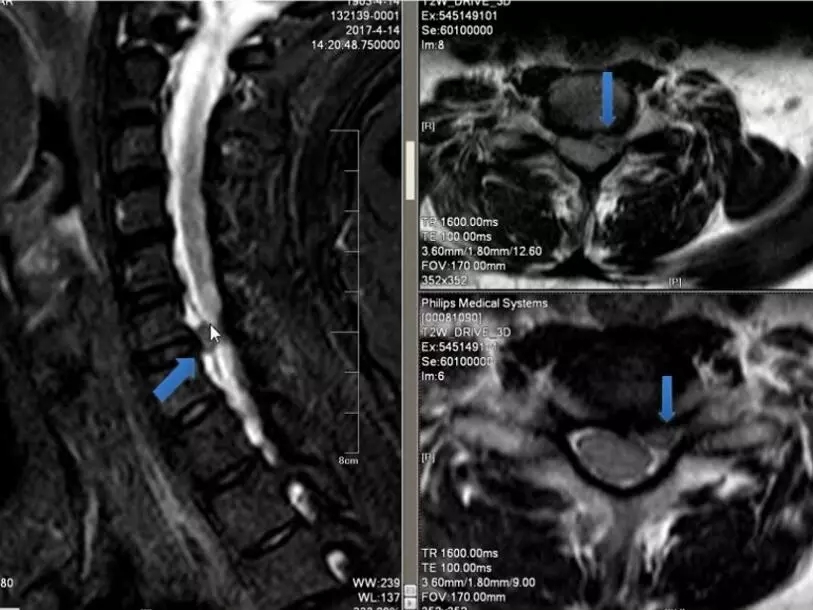

根性颈椎病,椎间盘脱出

这是一个椎间盘突出引起的神经根型颈椎病,我们在矢状面可以看到这里有突出的椎间盘,在横断面也可以看到突出的椎间盘压迫了神经根,治疗原则主要是前路,摘取致压物,还有进行椎间融合,但目前也有经椎间孔镜通后路进行致压物的摘取。根性颈椎病的预后,如果是单纯的椎间不稳,椎间盘突出或者脱出的,预后比较好,如果是由于钩椎关节增生导致根袖黏连,这样的病例症状会发生延续,预后较差。如果是广泛性的骨质增生造成的压迫,发生了变性,预后则更差